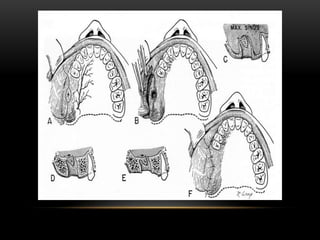

Treatment of chronic Oroantral communication: there are two ways which involves surgical

procedures that can be used for this treatment (Doran 2008:2).

1. Buccal advancement flap (most common)

• Broad base providing good blood supply.

• Periosteum scored parallel to base of flap to allow greater mobilisation of flap.

• OAC / OAF mucosa excised.

• Alveolus reduced in height.

• Palatal mucosa incised & mobilized.

• Flap brought across defect & secured with sutures.

• There must be no / minimal tension on the flap.

• Disadvantage of reduction of buccal vestibular depth; reshapes in 4 -8 weeks as flap adapts to

underlying bone.

2. Palatal Rotational Advancement Flap (Doran 2008:2).

• Advantages of insured vascularity (greater palatine vessels)& thickness of tissue more

like crest of ridge.

• Buccal mucosa incised & mobilised.

• Allows for the maintenance of the vestibularsulcus depth.

• Indicated in cases of unsuccessful buccal flap closure.

• Disadvantage of raw surface left behind; can be covered with a plate or Coe-pack.